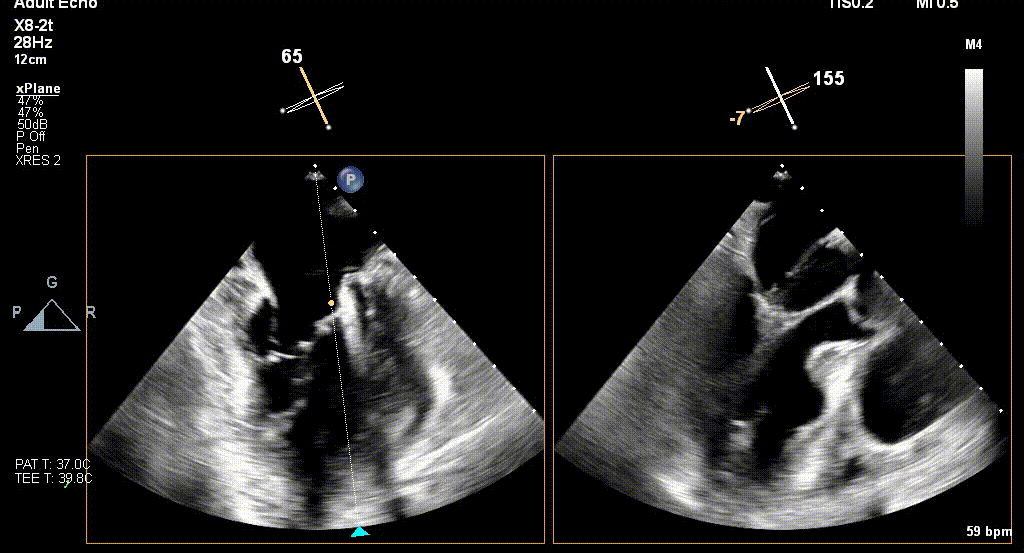

术前TEE评估

原发性MR,交界C1区脱垂,反流程度4+;二尖瓣瓣口面积3.88cm²,平均跨瓣压差2mmHg;二尖瓣前叶(A1)长度16.2mm,二尖瓣后叶长度(P1)长度9.9mm,脱垂高度6mm。